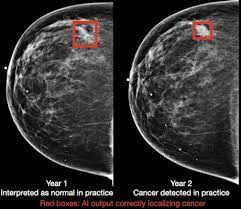

How Many Breast Cancers Are Found By Mammogram : Breast Cancer Screening In Singapore All About Mammograms Health Plus : The sensitivity of screening mammography in the united states is 72.4% to 80.1% 9,10;. Half of women have dense breast tissue, and for those women, mammogram may not be enough. It's so important to listen to the messages our bodies are telling. The sensitivity of screening mammography in the united states is 72.4% to 80.1% 9,10; Breast cancers found by screening are generally at an early stage. It's rare for women to get cancer within a year of mammography, but it does.

Health, united states, 2019, table 33. Mammography women diagnosed with breast cancer after having yearly mammograms were diagnosed with cancers that were smaller and less advanced than women who had mammograms every 2 years, according to results from a small study. The current evidence suggests that breast screening reduces the number of deaths from breast cancer by about 1,300 a year in the uk. Accuracy of mammograms mammography is good at finding breast cancer, especially in women ages 50 and older. Breast cancer is primarily a women's disease, but it does affect men.

1 from Health, united states, 2019, table 33. Little attention has been paid to how interval breast cancers are ultimately discovered. It is the best screening tool available today to find breast cancer early. It can also detect calcifications The mammogram itself only takes a few minutes, but the appointment may last about 30 minutes. If you have dense breast tissue, the odds of the cancer being missed on mammography start going up. Percent of women aged 40 and over who had a mammogram within the past 2 years: It's rare for women to get cancer within a year of mammography, but it does.

Overall, the sensitivity of mammography is about 87 percent 31 . After a mammogram that didn't show anything, and a sonogram that found the lump, i was diagnosed with stage 2 breast cancer. Screening with 3d mammography seemed to find breast cancers at an earlier, more treatable stage in these younger women. Breast cancer is primarily a women's disease, but it does affect men. Breast screening with a mammogram can help to find breast cancers early when they are too small to see or feel. These breast cancers may never grow and some may even shrink on their own. Half of women have dense breast tissue, and for those women, mammogram may not be enough. For women age 40 to 49: It's so important to listen to the messages our bodies are telling. Breast cancers found by screening are generally at an early stage. Accuracy of mammograms mammography is good at finding breast cancer, especially in women ages 50 and older. Little attention has been paid to how interval breast cancers are ultimately discovered. It's rare for women to get cancer within a year of mammography, but it does.

We estimate about 15 percent of breast cancers are diagnosed during a reasonable interval after a negative mammogram. But a new study published in the new. The sensitivity of screening mammography in the united states is 72.4% to 80.1% 9,10; The mammogram itself only takes a few minutes, but the appointment may last about 30 minutes. This means mammography correctly identifies about 87 percent of women who truly have breast cancer.

Mammograms miss about 15 percent of. Breast cancer is primarily a women's disease, but it does affect men. Half of women have dense breast tissue, and for those women, mammogram may not be enough. It can find breast cancer when it is very small, even too small to feel. The current evidence suggests that breast screening reduces the number of deaths from breast cancer by about 1,300 a year in the uk. The health professionals who take mammograms are called mammographers. Health, united states, 2019, table 33. For example, they aren't 100% accurate in showing if a woman has breast cancer: Overall, the sensitivity of mammography is about 87 percent 31 . This type of mammogram is called a diagnostic mammogram. Thus, approximately 20% to 28% of breast cancers are interval cancers. Mammography women diagnosed with breast cancer after having yearly mammograms were diagnosed with cancers that were smaller and less advanced than women who had mammograms every 2 years, according to results from a small study. The mammogram itself only takes a few minutes, but the appointment may last about 30 minutes.